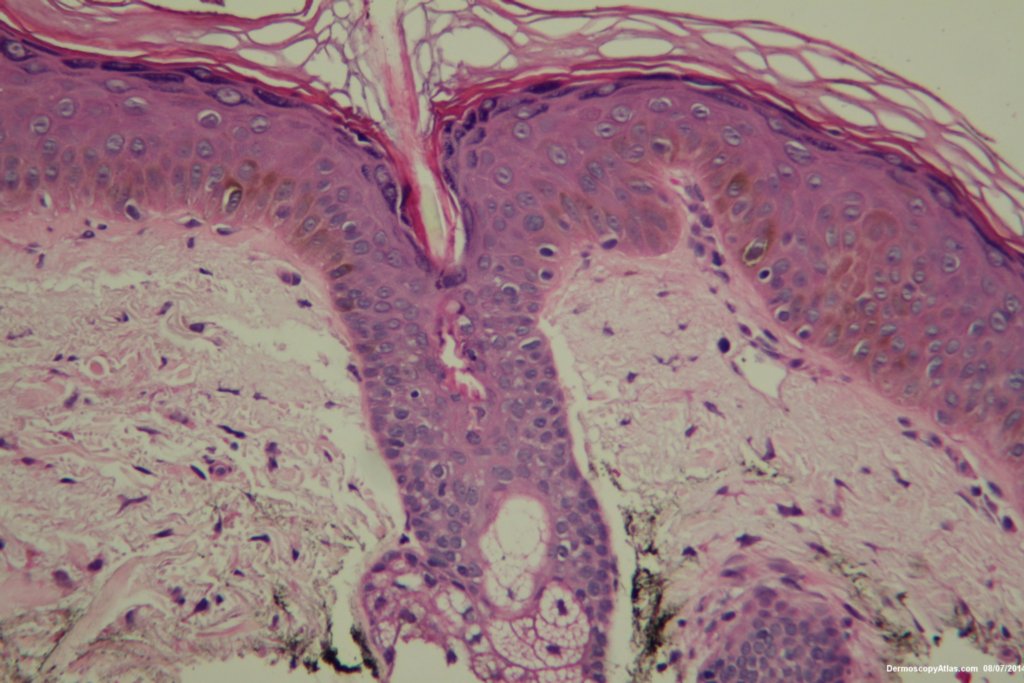

Image Number #3354 (Lentigene)

Site: Cheek

Diagnosis: Lentigene

Description: Enlarging brown patch on the cheek

This lady had a slowly growing pigmented lesion on her cheek . The clour was varying a bit. The dermatoscopy did not show grey circles or other features of early lentigo maligna. Her shave biopsy showed only increased melanin in basal keratinocytes. This was a lentigene. It was lasered off for cosmetic reasons.